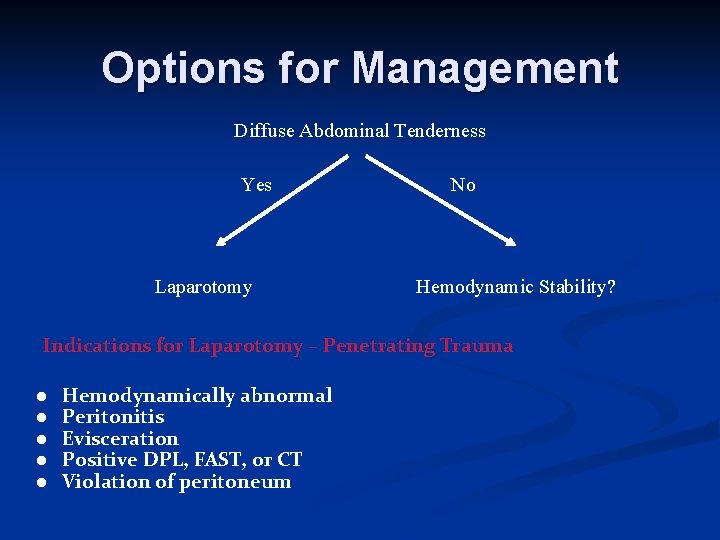

Options for Management Diffuse Abdominal Tenderness Yes Laparotomy No Hemodynamic Stability? Indications for Laparotomy – Penetrating Trauma ● ● ● Hemodynamically abnormal Peritonitis Evisceration Positive DPL, FAST, or CT Violation of peritoneum

Options for Management n Hemodynamically stable penetrating injury Serial Observation Wound Exploration DPL CT scan +/- Contrast Laparoscopy Laparotomy Ultrasound/echo – cardiac box Pericardial window – cardiac box